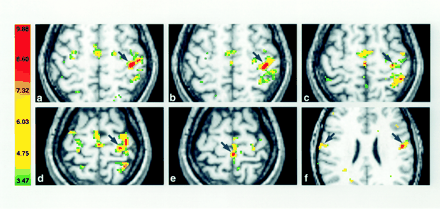

Activation in contralateral M1 (arrows) displayed in axial sections for one subject in the first session. The right side of the sections corresponds to the left hemisphere, and the numbers in the color bar correspond to t values.

A and B, The fingers (A) and hand (B) are in almost identical locations (z plane, +58).

C and D, The wrist (C) and elbow (D) representations are located more medially, superior and posterior along the course of M1 (z plane, +59 and +61, respectively).

E and F, Note the considerable overlap of activated volumes within the arm and the clear separation of the foot (E) and tongue (F) (z plane, +66 and +28, respectively).

Activation of contralateral M1 in the second session in the same subject as in Figure 1. A comparison with the images in Figure 1 reveals a high degree of reproducibility in the somatotopy despite variations in the activated volumes.

A and B, Fingers (A) and hand (B).

C and D, Wrist (C) and elbow (D).

E and F, Foot (E) and tongue (F).

Cortical maps acquired during the execution of all six movements in one representative subject are shown in Figure 1. The considerable overlap of activated volumes for the forearm movements (fingers, hand, wrist, and elbow) can be seen. Quantitative single-subject analysis in all individuals and in both sessions revealed a mean percentage volume overlap ranging from 14% for the fingers with the elbow to 86% for the fingers with hand opening and closing (Table 2).

When the volumes of activation of both imaging sessions were compared within subjects, considerable variations were revealed for each movement within the contralateral M1, as can be seen in the means and SDs listed in Table 3. The paired t tests revealed that these variations in volume were not significantly different across sessions. Figure 2 displays the cortical maps obtained for the six movement types during the second session in the same subject as in Figure 1. The intraindividual variability in the extent of the activated volumes (when compared with the findings in Fig 1) is obvious.